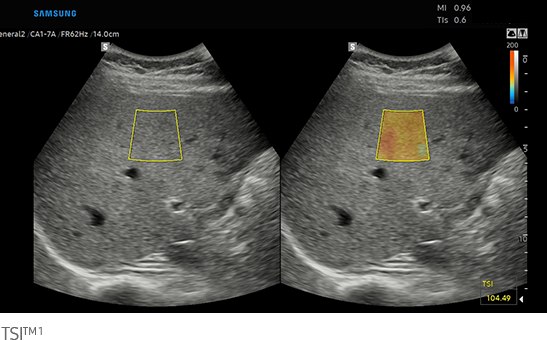

Quantitative measurement of liver fat

with ultrasound signal

TAI™ ¹ provides a quantitative tissue attenuation measurement to assess steatotic liver changes.

TSI™ ¹ provides a quantitative tissue scatter distribution measurement to assess steatotic liver changes.